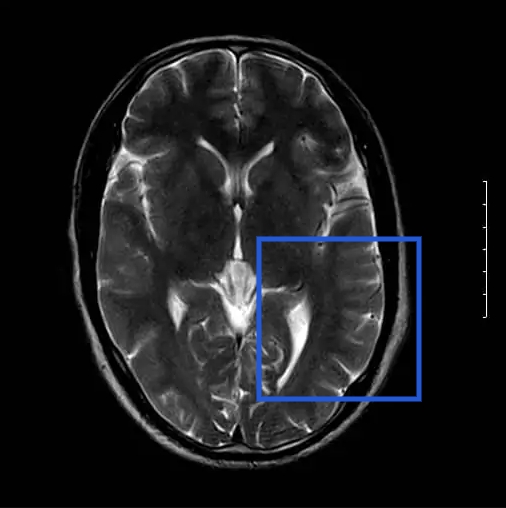

Nachbeurteilung von Kopf-MRTs auf fokale cortikale Dysplasien (FCDs).